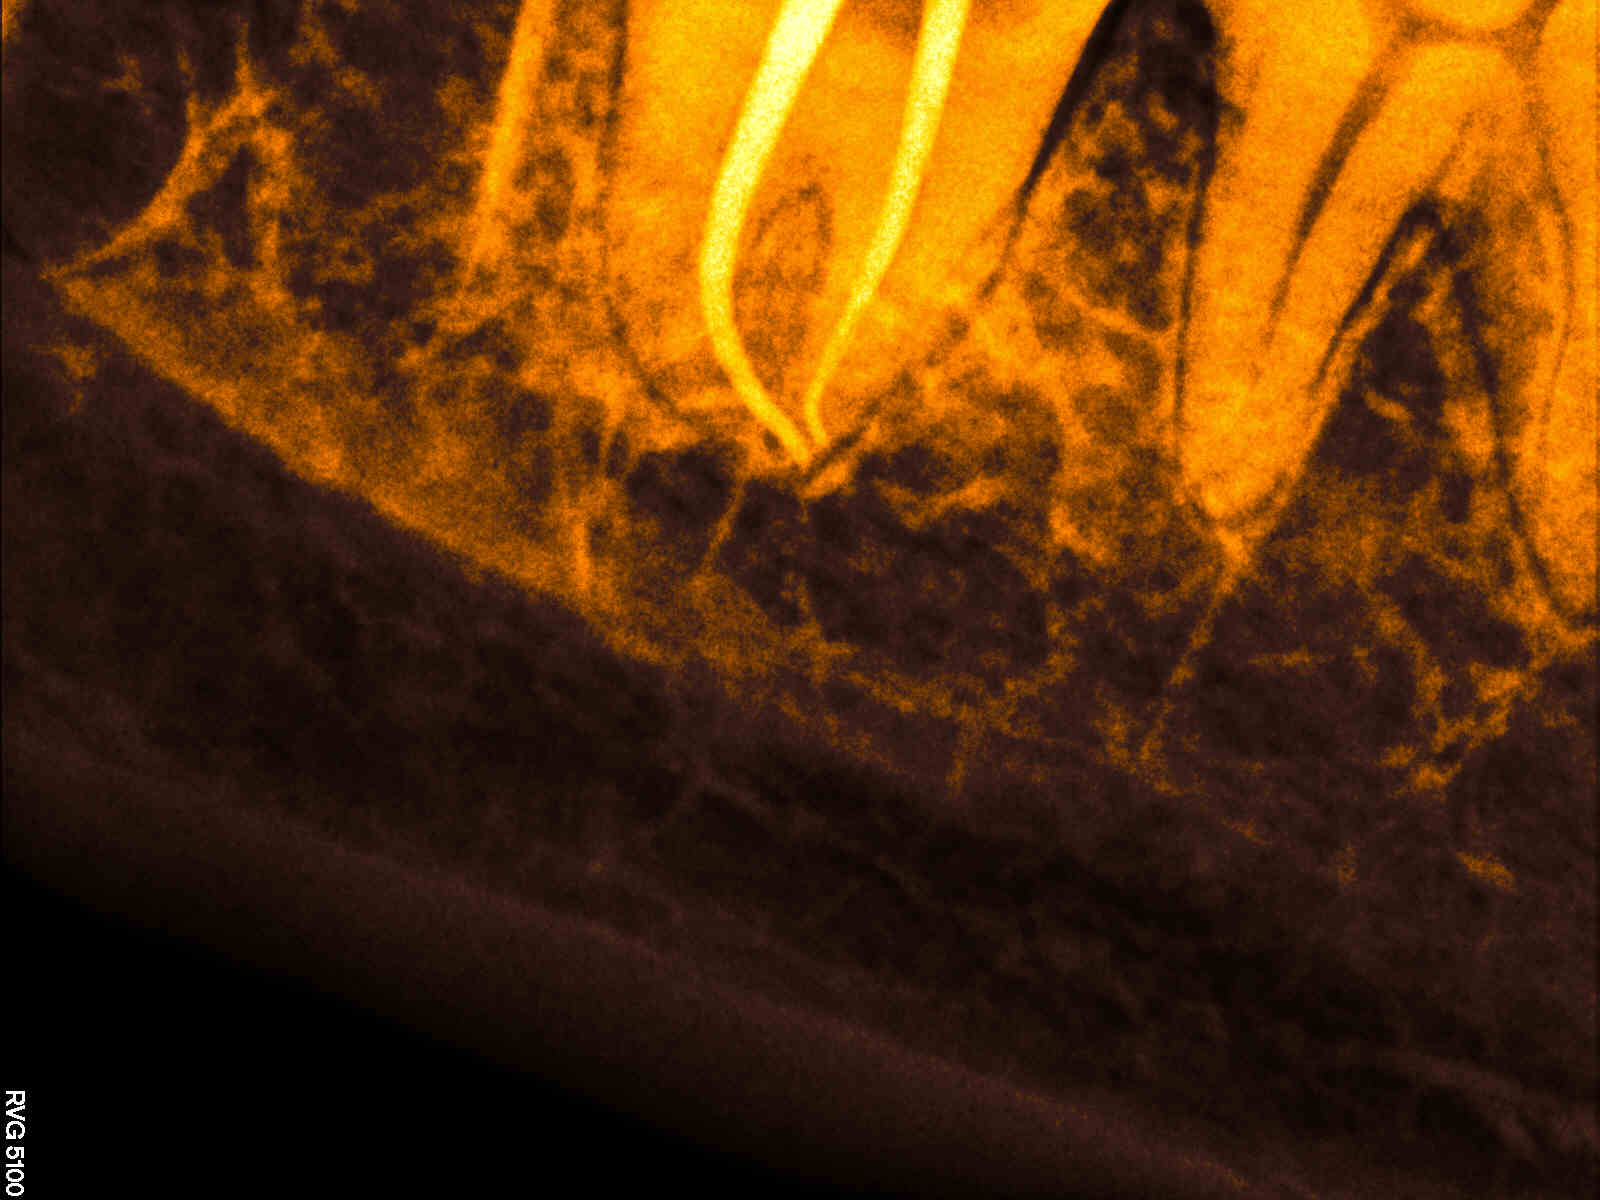

An X-ray is taken initially to fully understand the shape of the root canal and to check for infection in and around the affected area of the tooth.

root canal treatment steps